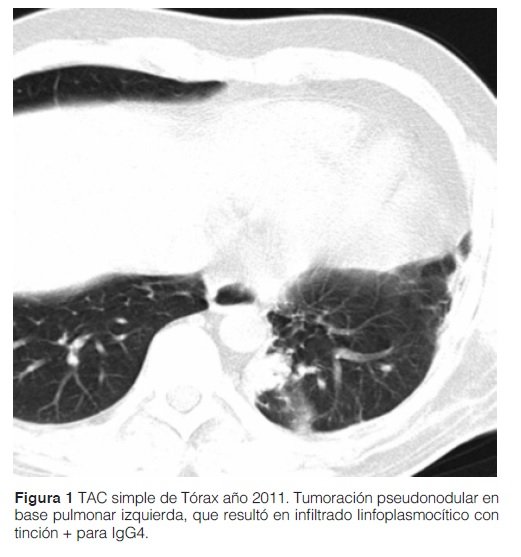

Paciente de sexo masculino de 32 años, sin patología de base, que consulta por pérdida de peso, fiebre de origen desconocido (FOD), que persistía tras antibioticoterapia empírica durante su manejo ambulatorio. Como screening de FOD se procedió a la realización de pruebas laboratoriales y al barrido tomográfico donde se halló el pseudotumor pulmonar, que fue la principal pieza diagnóstica. En los resultados laboratoriales no se encontraron datos llamativos; incluyeron: valores normales o negativos, según corresponda, para hemograma (excepto por eosinofilia persistente de 25% en la fórmula relativa), hepatograma, urea, creatinina, PCR, VSG, ANA, Anti DNA, C3, C4, ANCA, rK39, HIV por Elisa, VHB y VHC, marcadores tumorales (CEA, Ca 125, Ca 19-9), policultivos y exámenes para tuberculosis (TB). Aspectos imagenológicos: Por tomografía axial computarizada (TAC) simple de tórax se informó tumoración pseudonodular de 35 mm en base pulmonar izquierda (Ver figura 1). En PET TC: hipercaptación en la zona del tumor referido. No se captaron adenopatías.